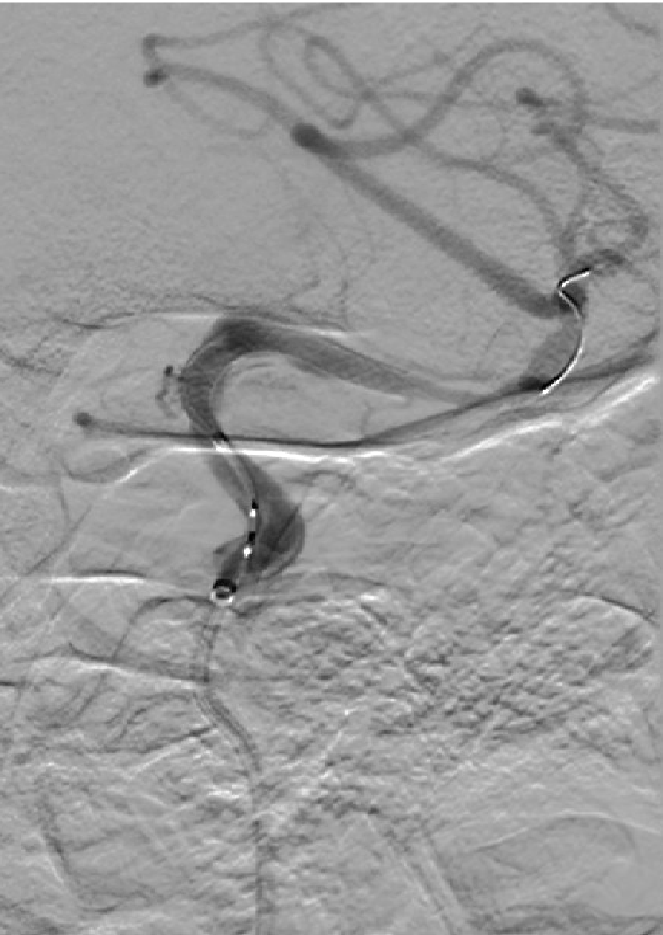

Pipeline™ Flex 血流导向密网支架于密网支架充分打开,所以从外缘向内缘回拉,让密网支架位于血管中轴。

Pipeline™ Flex 血流导向密网支架密网支架充分打开。

支架内按摩。

术后图像显示支架打开及贴壁良好。